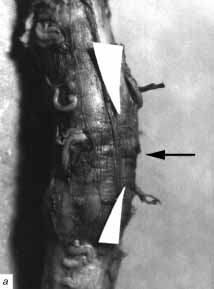

Рис. 1. Больной М., 23 лет. Сочетанная травма головы

и позвоночника, в т. ч. перелом тел С5-6 позвонков, дуг 5-го шейного позвонка

с двух сторон в области мест прикрепления правого и левого поперечных

отростков.

Больному на 2-е сут после травмы произведена операция: корпорэктомия С5-6,

передняя декомпрессия спинного мозга и корешков C5-6-7 с двух сторон,

передний комбинированный шейный спондилодез С4-7 аутокостью и титановой

пластиной. Задняя продольная связка в проекции 5 шейного позвонка расслоена

на участке длиной 1 см, края расслоения пропитаны кровью.

а - в проекции 5 шейного позвонка на спинном

мозге имеется циркулярная полоса (обозначена стрелкой) от сдавления дужкой

шириной 0,3 см, вещество спинного мозга на этом уровне несколько западает,

тускловатое, синюшного вида. На разрезе оно было со стертым рисунком строения

за счет множественных, сливающихся между собой, кровоизлияний. Спинной

мозг на всем протяжении выше полосы сдавления и на протяжении 2 см ниже

ее увеличен в диаметре, дрябловат, в отличие от дистальных участков, где

он был обычного диаметра, плотный, без кровоизлияний.